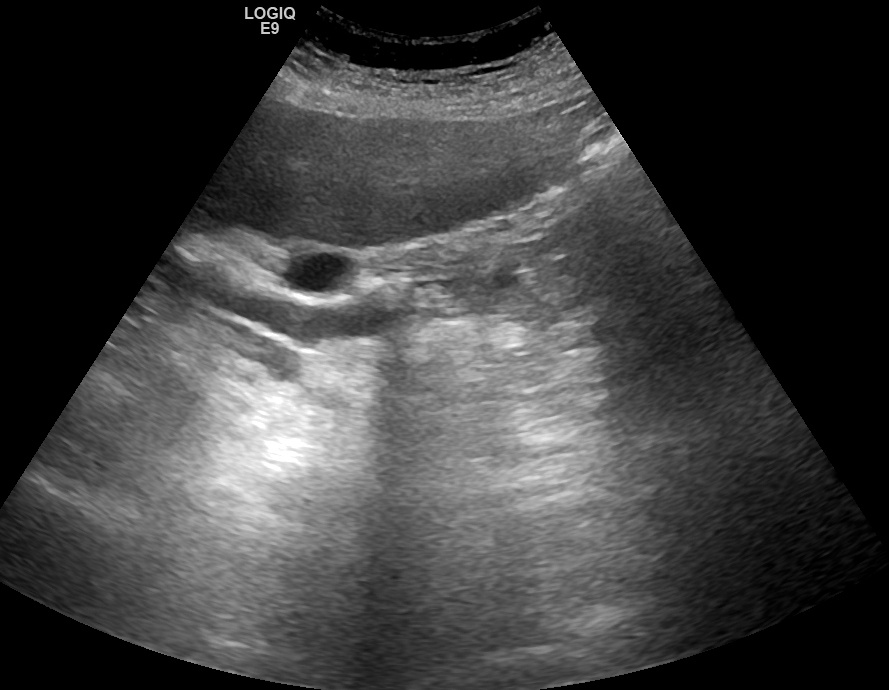

При ультразвуковом исследовании был выявлен значительно расширенный холедох, но вначале камень не был обнаружен. Такое возможно, когда конкремент находится в зоне, где общий желчный проток перекрыт двенадцатиперстной кишкой, или если камень спустился к самому Фатерову соску. В подобной ситуации может помочь следующий методический прием: пациента надо положить на правой бок, чтоб он полежал так некоторое время (это время можно посвятить изучению левой почки и селезенки) а потом снова просканировать холедох, лучше даже в этом же положении пациента на правом боку. Конкремент под действием силы гравитации смещается ближе к воротам печени и становится видимым, что и было применено в данном случае.

Рис. 01. Конкремент в дистальном отделе расширенного холедоха с несколько неотчетливой дистальной акустической тенью.

Рис. 03. Конкремент в дистальном отделе расширенного холедоха

Камень достаточно крупный, до 16 мм. Обращает на себя внимание, что дистальнее камня холедох продолжает оставаться расширенным, что косвенно свидетельствует, что выявленный конкремент - не единственный.